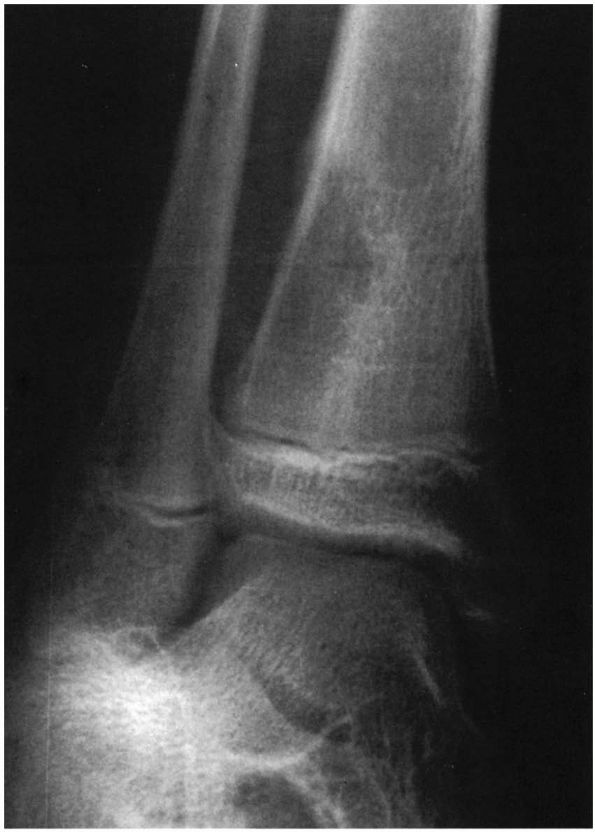

![]() |

FIGURE 5-4. Eight-year-old boy with osteomyelitis of the pubis and a pelvic abscess. (A) AP radiograph of the pelvis of this child demonstrating no bony abnormalities. (B) Technetium-99m bone scan demonstrating increased uptake of the isotope in the region of the right pubis. (C) CT scan through the obturator region of the pelvis demonstrating an abscess in the obturator region of the right hemipelvis.